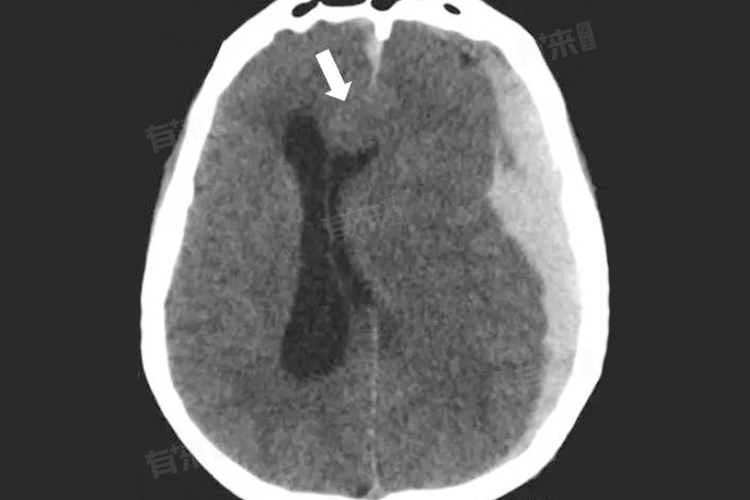

1、影像学检查:如CT或MRI扫描,用于评估颅内压变化及脑组织移位情况,是诊断和随访脑疝的关键工具。